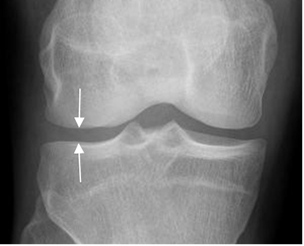

El cartílago y la cavidad articular son radiotransparentes y forman el espacio articular radiológico. (Fig 3).

Fig 3. Espacio articular normal.

Rx AP. Espacio articular, entre las estructuras óseas.

El derrame articular y laxitud ligamentaria, producen distensión de la cápsula y aumento del espacio. Por el contrario el daño del cartílago ocasiona disminución del espacio. (2).